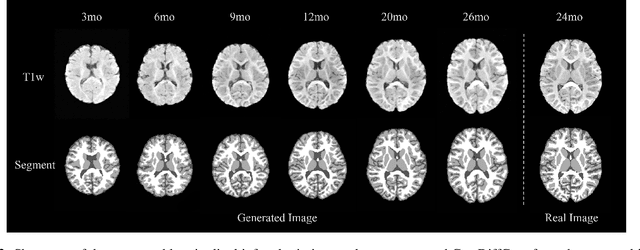

Abstract:Early infancy is a rapid and dynamic neurodevelopmental period for behavior and neurocognition. Longitudinal magnetic resonance imaging (MRI) is an effective tool to investigate such a crucial stage by capturing the developmental trajectories of the brain structures. However, longitudinal MRI acquisition always meets a serious data-missing problem due to participant dropout and failed scans, making longitudinal infant brain atlas construction and developmental trajectory delineation quite challenging. Thanks to the development of an AI-based generative model, neuroimage completion has become a powerful technique to retain as much available data as possible. However, current image completion methods usually suffer from inconsistency within each individual subject in the time dimension, compromising the overall quality. To solve this problem, our paper proposed a two-stage cascaded diffusion model, Cas-DiffCom, for dense and longitudinal 3D infant brain MRI completion and super-resolution. We applied our proposed method to the Baby Connectome Project (BCP) dataset. The experiment results validate that Cas-DiffCom achieves both individual consistency and high fidelity in longitudinal infant brain image completion. We further applied the generated infant brain images to two downstream tasks, brain tissue segmentation and developmental trajectory delineation, to declare its task-oriented potential in the neuroscience field.